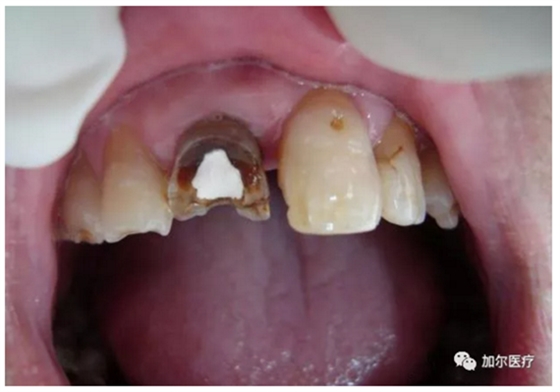

蛀牙連一半的牙冠都沒了,但是牙齒又不疼,而且還有些發(fā)黑,牙醫(yī)拍片檢查后才知道得做根管治療,那時牙痛真要人命,可是怎么判斷牙髓壞死?

1、牙髓病死最大的感知就是牙齒沒有什么感覺,連吃飯冷熱酸甜一點反應(yīng)都沒有,另外還會經(jīng)常出血,一般深齲傷及牙髓剛開始是慢性牙髓炎。

2、到后來牙齒沒有了營養(yǎng)來源,咬過硬東西時牙冠一不小心就會崩壞。

1、無論是急性牙髓炎還是慢性牙髓炎都必須做根管治療,任何藥物無法治愈牙髓炎,既然牙髓炎是因病變牙髓而起,局部麻醉后,根管治療時抽出牙髓,牙齒自然是不會痛。

2、前提是全部牙髓清理干凈,就得多次封藥消毒,確定沒有不適感后才可做樹脂填充,最后戴上烤瓷牙冠保護脆弱原牙。